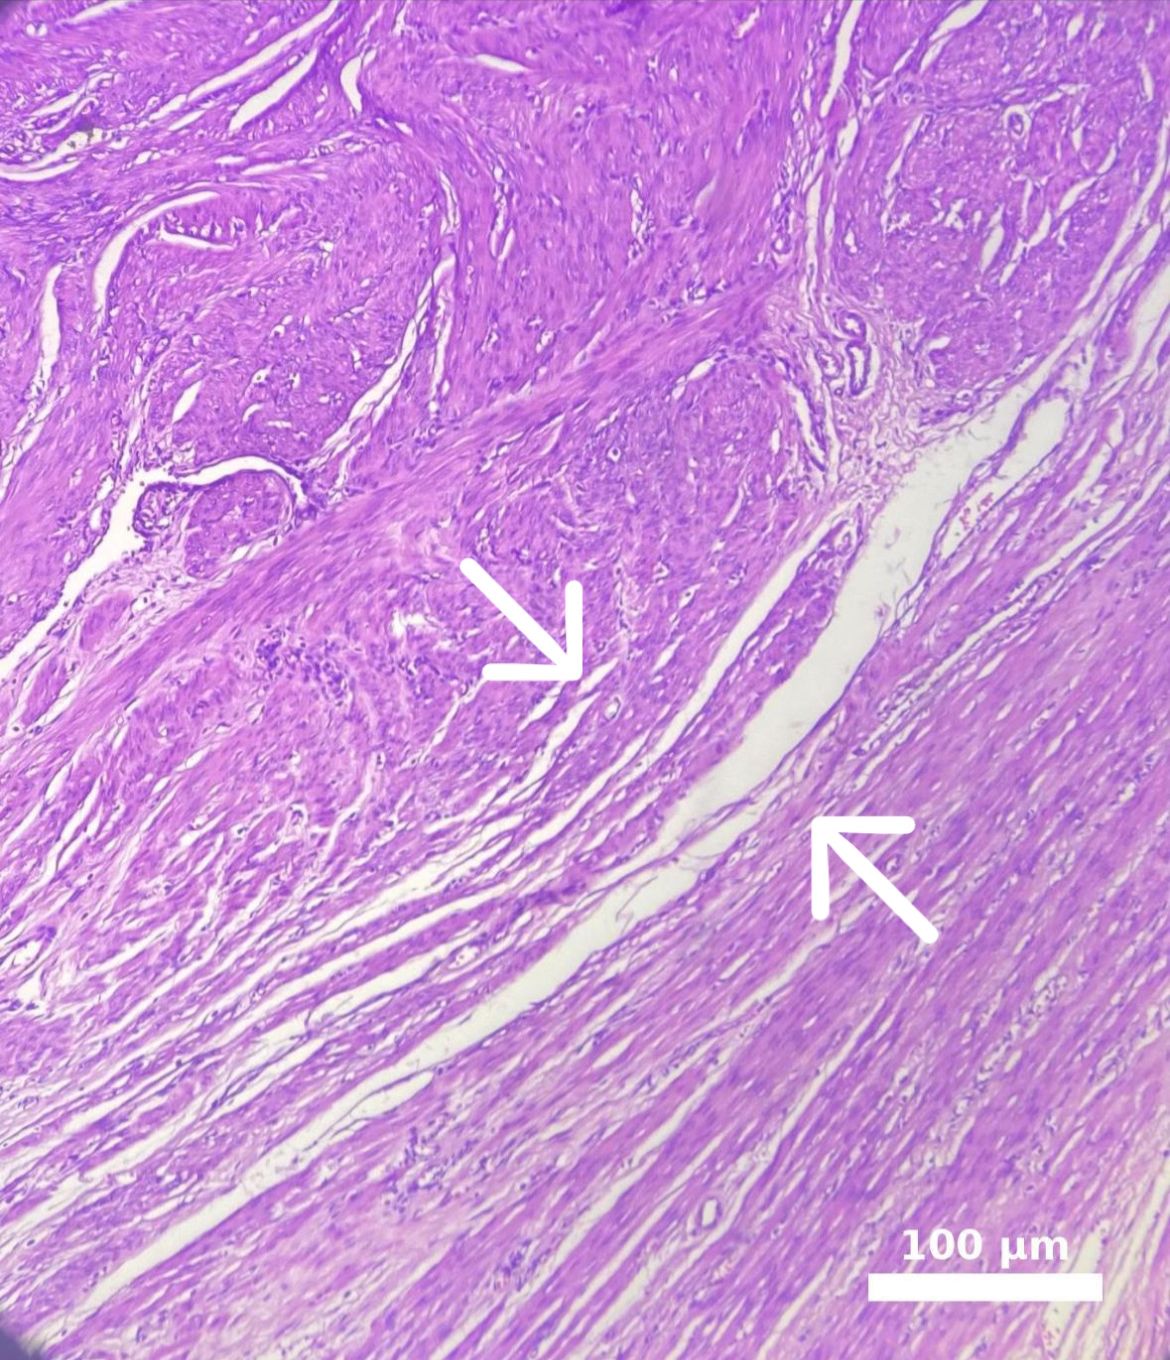

Myoma patients presented to the gynecology clinic due to complaints of prolonged menstrual bleeding and dysmenorrhea. During the transvaginal ultrasound (TVUS) examination, an intramural myoma was detected in 105 patients, submucous myoma in 35 patients, and intramural and submucous myoma detected in 60 patients (Figs. 1,2). Ovarian endometriosis was present in 105 of these patients. These patients were operated on by gynecologists. Pathology results were compatible with leiomyoma uteri (Fig. 3). The hospital stay was for 2 days. In the postoperative period, surgical site infection developed in 6 patients and hematoma at the incision line in 3 patients. Hematoma drainage was performed in only 1 patient. Surgical site infection resolved with antibiotic treatment. During the follow-up period, abdominal wall endometrioma developed only in the patient who underwent intervention due to myomectomy + ectopic pregnancy at the same time (0.5%). Characteristics of the 3 groups are shown in Tables 3,4.

Fig. 3. Microscopic appearance of intramural myoma. The white line marked with a white arrow in the image delineates the border between the leiomyoma and the adjacent myometrium. Endometrioma tissue is visible on the left side. The myometrium in the lower right corner appears distorted due to pressure, while an intramural myoma is observed in the upper left corner. Scale bar: 100 μm (H&E, hematoxylin and eosin,